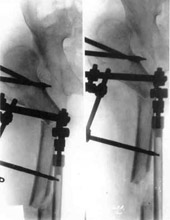

Schanz-Ilisarov's operation with elongation of hip.Schanz-Ilisarov's operation with elongation of hip.

Schanz-Ilisarov's operation with elongation of hip.

Schanz-Ilisarov's operation with elongation of hip.Results of treatment.

Results of treatment.